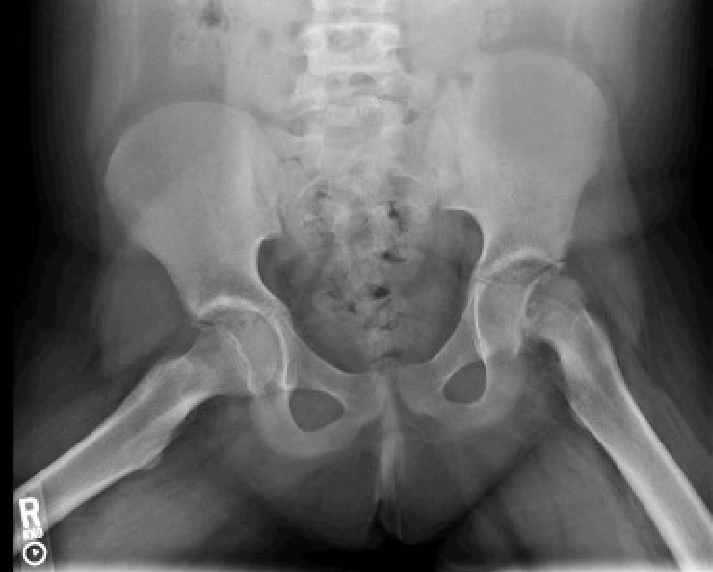

• 고관절 엑스레이 (생후 5~6개월 후부터 가능)

→ 대퇴 골두가 Hilgenreiner선보다 상방으로, Perkins 선보다 외측으로 전위